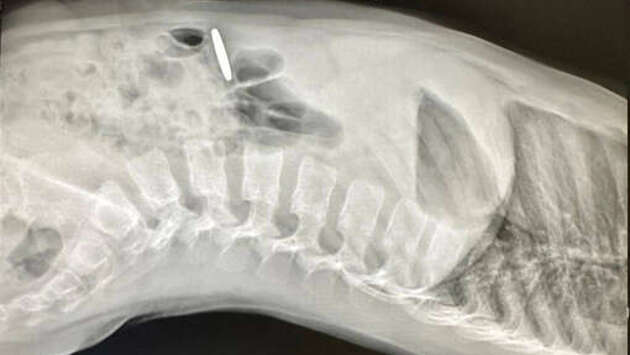

В Москве врачи помогли пятилетнему мальчику, который проглотил монету. Об этом сообщает Клиника доктора Рошаля. Родители маленького мальчика обратились за помощью в медицинское учреждение, где по результатам рентгенографии у него выявили в пищеварительном тракте инородный предмет. Им оказалась монета. Поскольку монета не продвигалась дальше, медики приняли решение провести эндоскопическое вмешательство. В ходе процедуры инородный объект был успешно извлечен. Как выяснилось, юный пациент проглотил монету номиналом 10 киргизских сомов. После проведенной манипуляции состояние ребенка не вызывало опасений, и вскоре его выписали домой. До этого российские врачи спасли дошкольницу с монетами в желудке. Вмешательство продлилось чуть более 30 минут, уже через три часа пациентку отпустили домой.